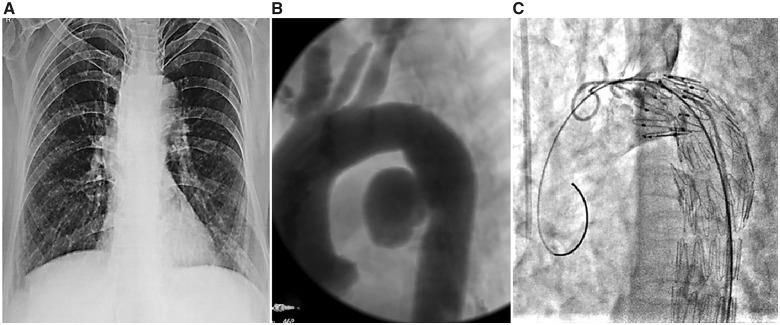

We hereby report two cases of AOF, who underwent successful emergency thoracic endovascular aortic repair (TEVAR) to control active bleed and exsanguination. Case 1, an elderly lady with atherosclerotic aneurysm had TEVAR followed by open surgery for oesophageal rent and necrosed left main bronchus. Case 2 had mycotic tubercular aneurysm who later had infected graft-stent following TEVAR.

我们在此报告两例AOF患者,他们成功接受了急诊胸主动脉腔内修复术(TEVAR)以控制活动性出血和失血。病例1是一位患有动脉粥样硬化性动脉瘤的老年女性,接受了TEVAR治疗,随后进行了食管裂口和左主支气管坏死的开放手术。病例2患有霉菌性结核性动脉瘤,在TEVAR后出现了感染的移植物支架。